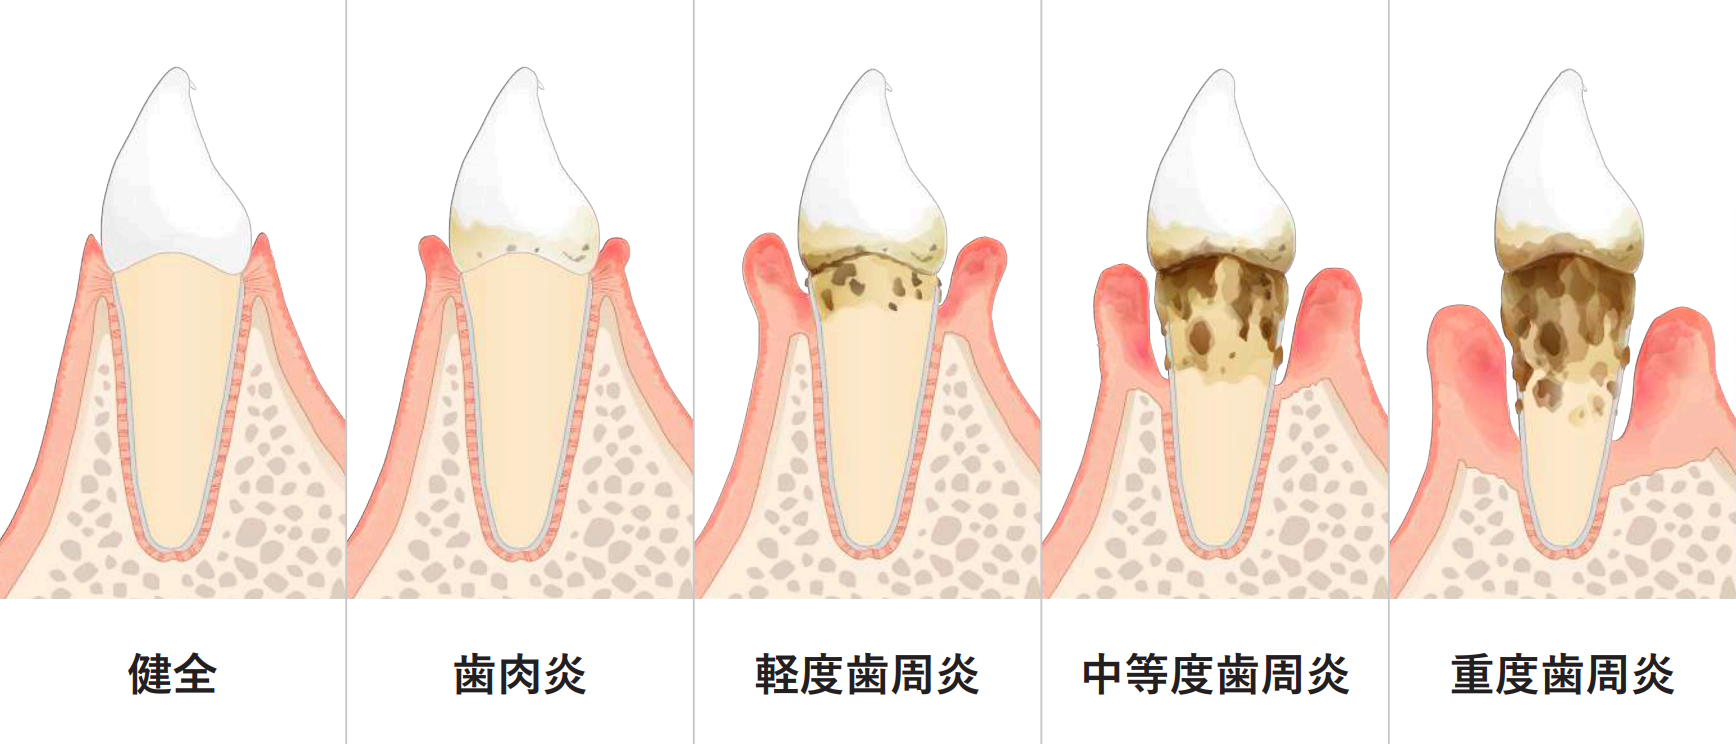

歯周病の進行

歯肉炎〜軽度の歯周炎

歯と歯ぐきの間にプラークがたまって歯ぐきが腫れ、出血しやすくなっています。歯を支える骨にはまだあまり影響がありません。

中度歯周炎

歯周ポケットが形成され、歯石が深部まで付着し、歯を支える骨を半分くらい失っています。

歯肉炎〜軽度の歯周炎

歯を支える骨がなくなってきて歯がぐらつき、このまま放っておくと歯が抜けてしまいます。歯ぐきが下がる、膿がでるなどの症状もみられます。